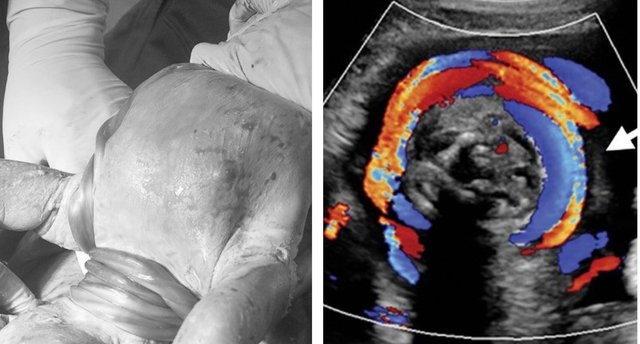

Hình ảnh dây rốn quấn cổ 5 vòng.

Trong quá trình theo dõi, các bác sĩ phát hiện thai nhi có dây rốn quấn cổ. Khi thấy thai nhi bị quấn tới 5 vòng, có hiện tượng cạn ối, nhận định tình hình nghiêm trọng nên sản phụ được các bác sĩ chỉ định mổ lấy thai ở tuổi thai 37 tuần 5 ngày.